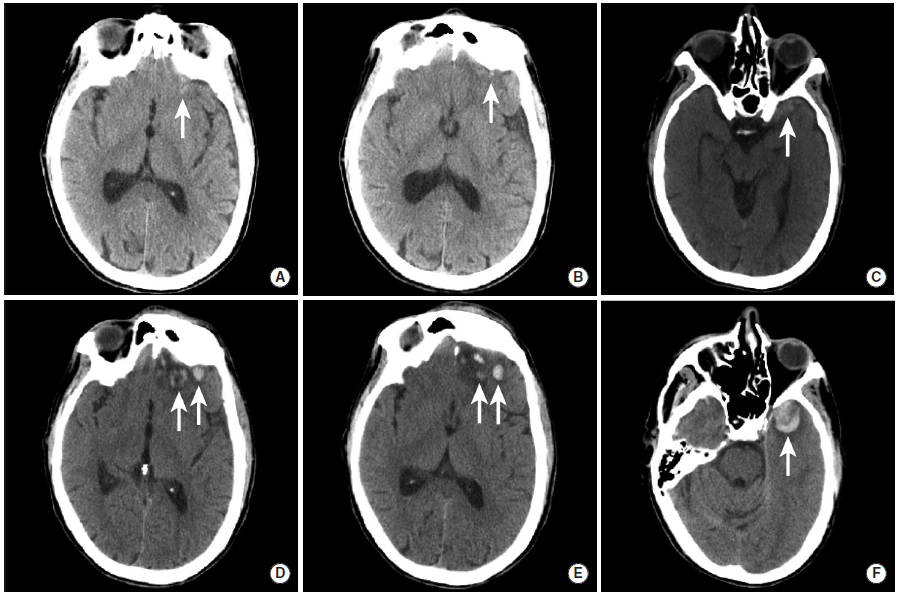

外伤性颅内出血

外伤性蛛网膜下腔出血

图1

本例为车祸导致的外伤性蛛网膜下腔出血。

图A:平扫CT显示脑沟内高密度影(长尾箭头),此外还可以看到左侧的硬膜下血肿(三角箭头)以及右顶骨处的帽状腱膜下血肿(虚线箭头)。

图B:MRI FLAIR序列同样可见脑沟内高信号,证实了蛛网膜下腔出血的存在,同时可见左侧硬膜下血肿和右侧帽状腱膜下血肿。

图C:GRE序列上,蛛网膜下腔出血和硬膜下血肿表现为低信号。

硬膜外血肿

图2

交通事故后创伤性硬膜下血肿两例。

图A、B:本例患者于意识状态低下时行影像学检查。右颞叶可见出血性脑实质挫伤(图A,三角箭头),同时左前颞叶前部可见半圆形硬膜外血肿灶(图A,长尾箭头)。骨窗影像可见硬膜外血肿附近存在非移位性颞骨骨折(图B,长尾箭头)。

图C、D:本例患者接受影像学检查时处于反应迟钝状态。平扫CT可见巨大的双凸面形硬膜外血肿(长尾箭头),并可见显著占位效应,导致左侧中线移位和大脑镰下疝(三角箭头),以及小脑幕切迹疝(虚线箭头)。

硬膜下血肿

图3

为了清楚地看到病变,CT的窗宽窗位做了一些调整。与硬膜下窗(图C、D)相比,病变在标准脑窗(图A、B)上不太明显。图中可见右前颞叶出血性挫伤和覆盖脑沟的蛛网膜下腔出血(三角箭头),骨板下可见弧形硬膜下血肿灶(长尾箭头)。

图4

本例患者由于巨大的硬膜下血肿引起了脑疝。平扫CT显示左侧巨大硬膜下血肿(长尾箭头),基底池受压消失(图A,三角箭头),大脑镰下疝形成(图B、C,三角箭头)和左侧小脑幕切迹疝(图C,虚线箭头)。